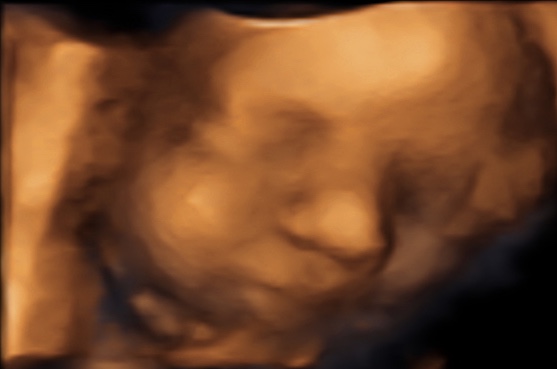

34 weken

Een echo na 34 weken.